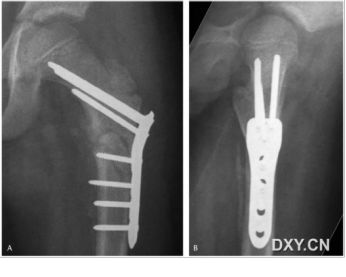

此处应用钢板有两种情况一是不会使用髓内固定,设备条件达不到;再就是理念落后见的病例少,交流少。此处外侧全部是长应力,钢板为张力钢板,内收肌力量强大,目前的钢板不能承受反复的弯曲应力,金属疲劳断裂失败率高,以下病例切开,钢丝捆绑进一步骨膜剥离,破坏了原始血肿,干扰骨愈合,都是失败原因

补救办法:剥削植骨髓内钉固定或动力髁钢板固定。

补救比较好